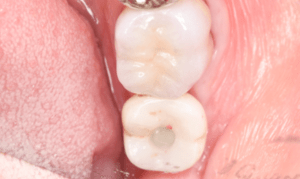

インプラント治療の症例7

レントゲン写真

- Before

- After

口腔内写真-1

口腔内写真-2

- 途中経過

| 年齢 | 40代・男性 |

|---|---|

| 主訴 | 主訴:インプラントがしたい 治療部位:左上5 |

| 治療内容 | インプラント埋入、GBR(骨造成) |

| 治療費 |

合計:726,000円 【内訳】 診断料:55,000円 埋入料:165,000円 GBR(骨造成):110,000円 サージカルガイド:55,000円 2次オペ:22,000円 仮歯:55,000円 上部構造(フルジルコニア):187,000円 IV:77,000円 (2024年4月現在) |

| 治療期間 | 1年3ヶ月 |

| リスク・副作用 | リスク・副作用 |

| 治療方針 | 骨が吸収され厚みが十分にないため、インプラント埋入と同時にGBR(骨造成)も行いました。 骨質は垂直的にはボリュームがありましたが、柔らかいため骨とインプラント体が結合するまでの待機期間を長めに設定しました。 |

| 特記事項 | 待機期間は2ヶ月~6ヶ月ほど待ち、インプラント体と骨が結合するのを待ちます。 結合できたことをレントゲンを撮影して確認します。 |

| 担当者所見 | 左上5は2017年の初診時から歯冠がないため抜歯を勧めましたが、ご本人の希望もあり、予後が悪いことも説明した上で被せ物を被せました。 2022年8月にその被せ物が外れ、虫歯にもなり、保存不可能だったため抜歯をしてインプラントを行いました。 |